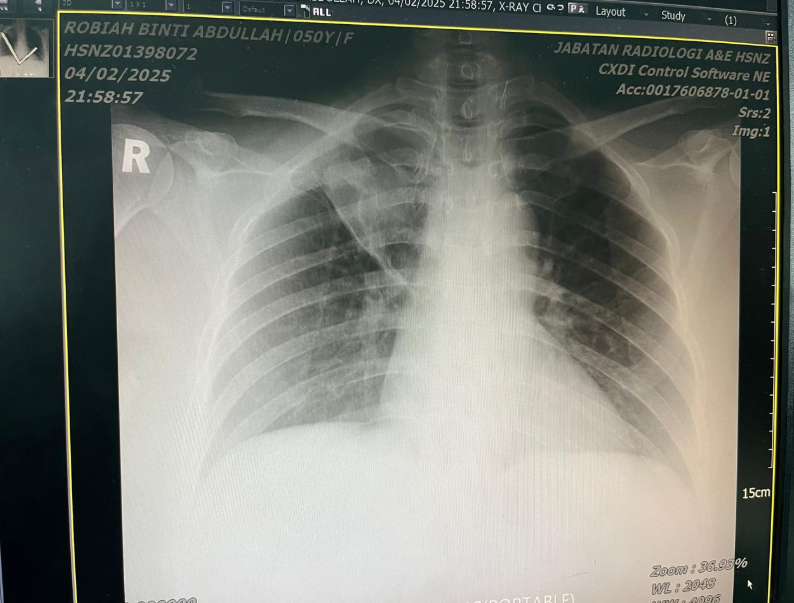

For five months, he had been dealing with a persistent, unrelenting cough that never seemed to improve. A CT scan in early July revealed a lung mass larger than 8 cm, with spread to the lymph nodes around the trachea and airways, along with fluid buildup (pleural effusion) in the right lung. Based on these findings, his condition was already considered clinically as Advanced Lung Cancer.

A follow-up CT scan performed one month after starting ECCT showed significant improvement, with the tumor shrinking by approximately 70–80% in volume compared with the scan taken four months earlier. Overall, his condition remained relatively good and stable.